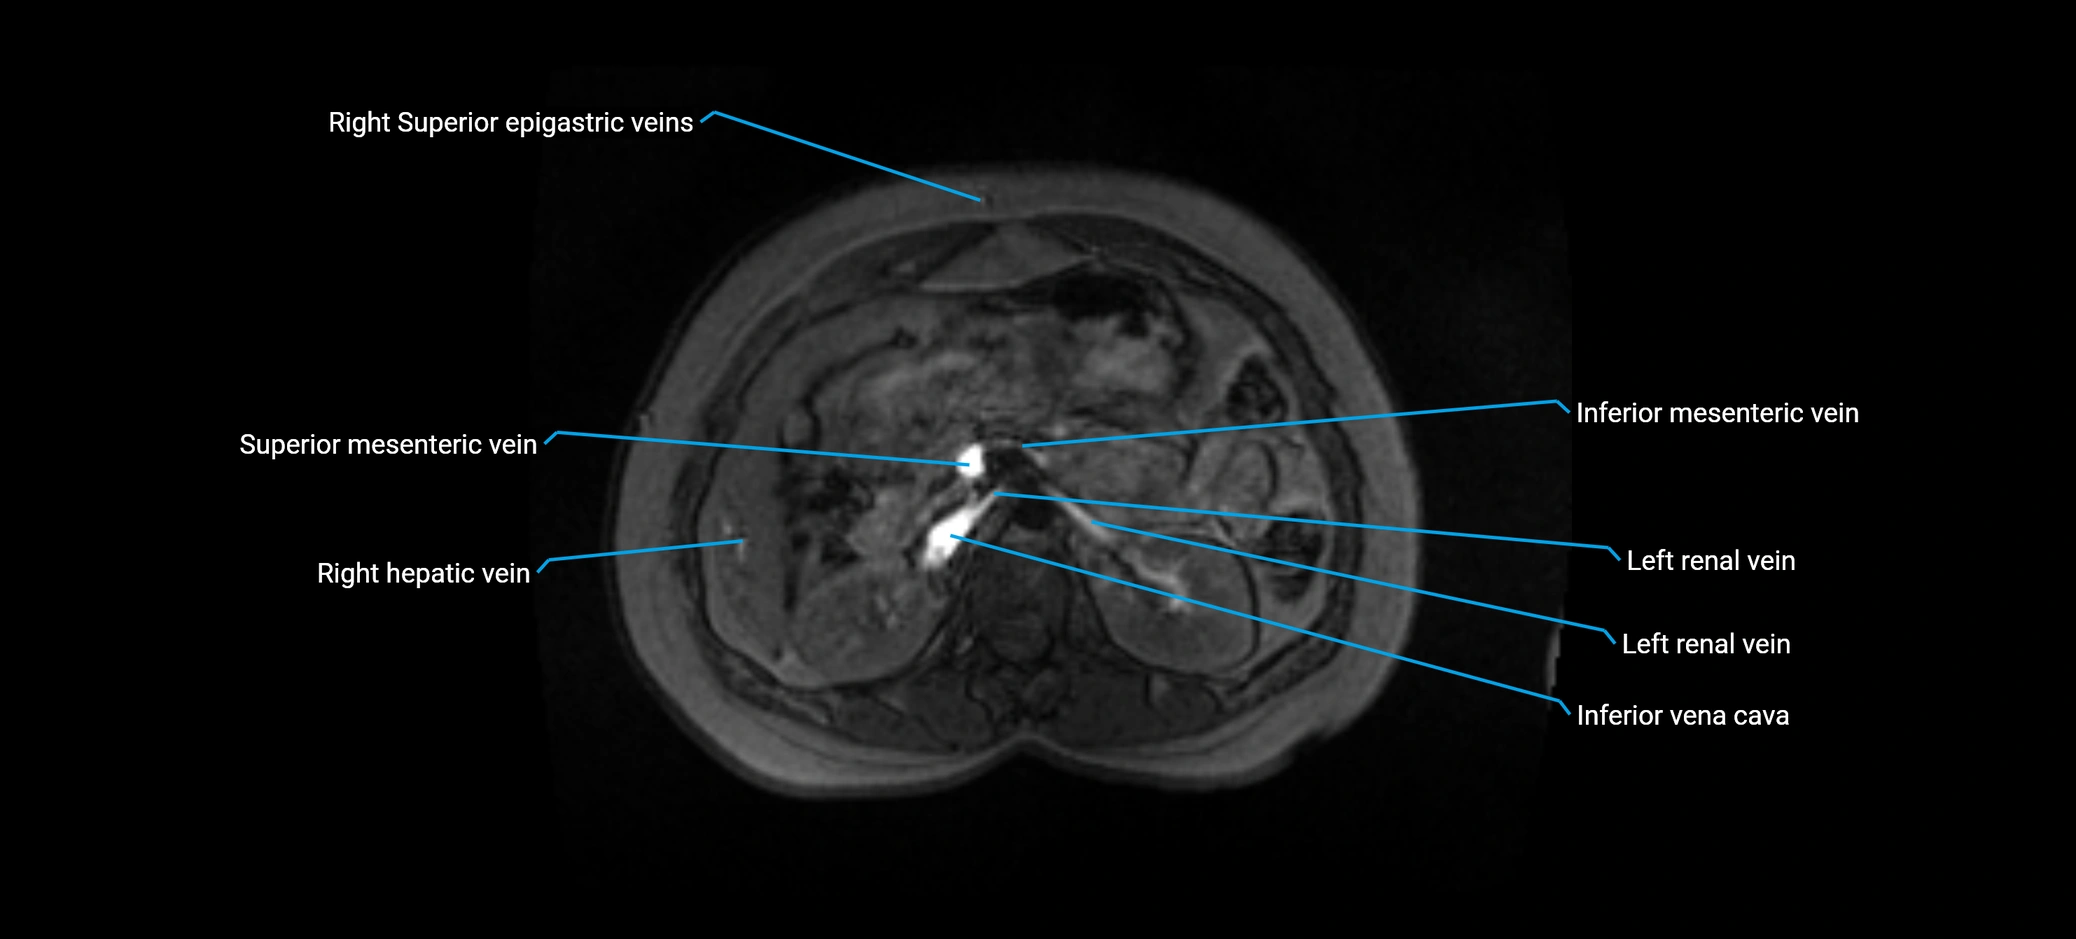

MRV TOF (Time-of-Flight MR Venography):

• Appears as a bright, high-signal vascular channel representing flowing blood

• Clearly shows branching pattern of right portal vein into anterior and posterior branches

• Best in coronal or axial reconstructions for segmental mapping

• No need for contrast, relies on flow-related enhancement

• Clearly delineates branching into segments V and VIII

• Best sequence for evaluating patency, caliber, and anatomic variants